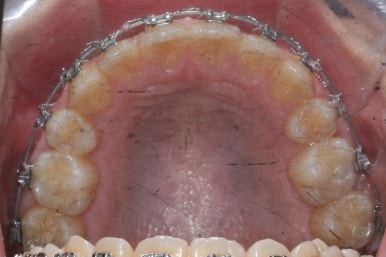

우선 위쪽 작은 어금니 부터 발치하였습니다.

송곳니 바로 뒤쪽의 작은 어금니를 뽑은 것을 보실 수 있겠습니다.

이제는 아래쪽 작은 어금니도 뽑았습니다.